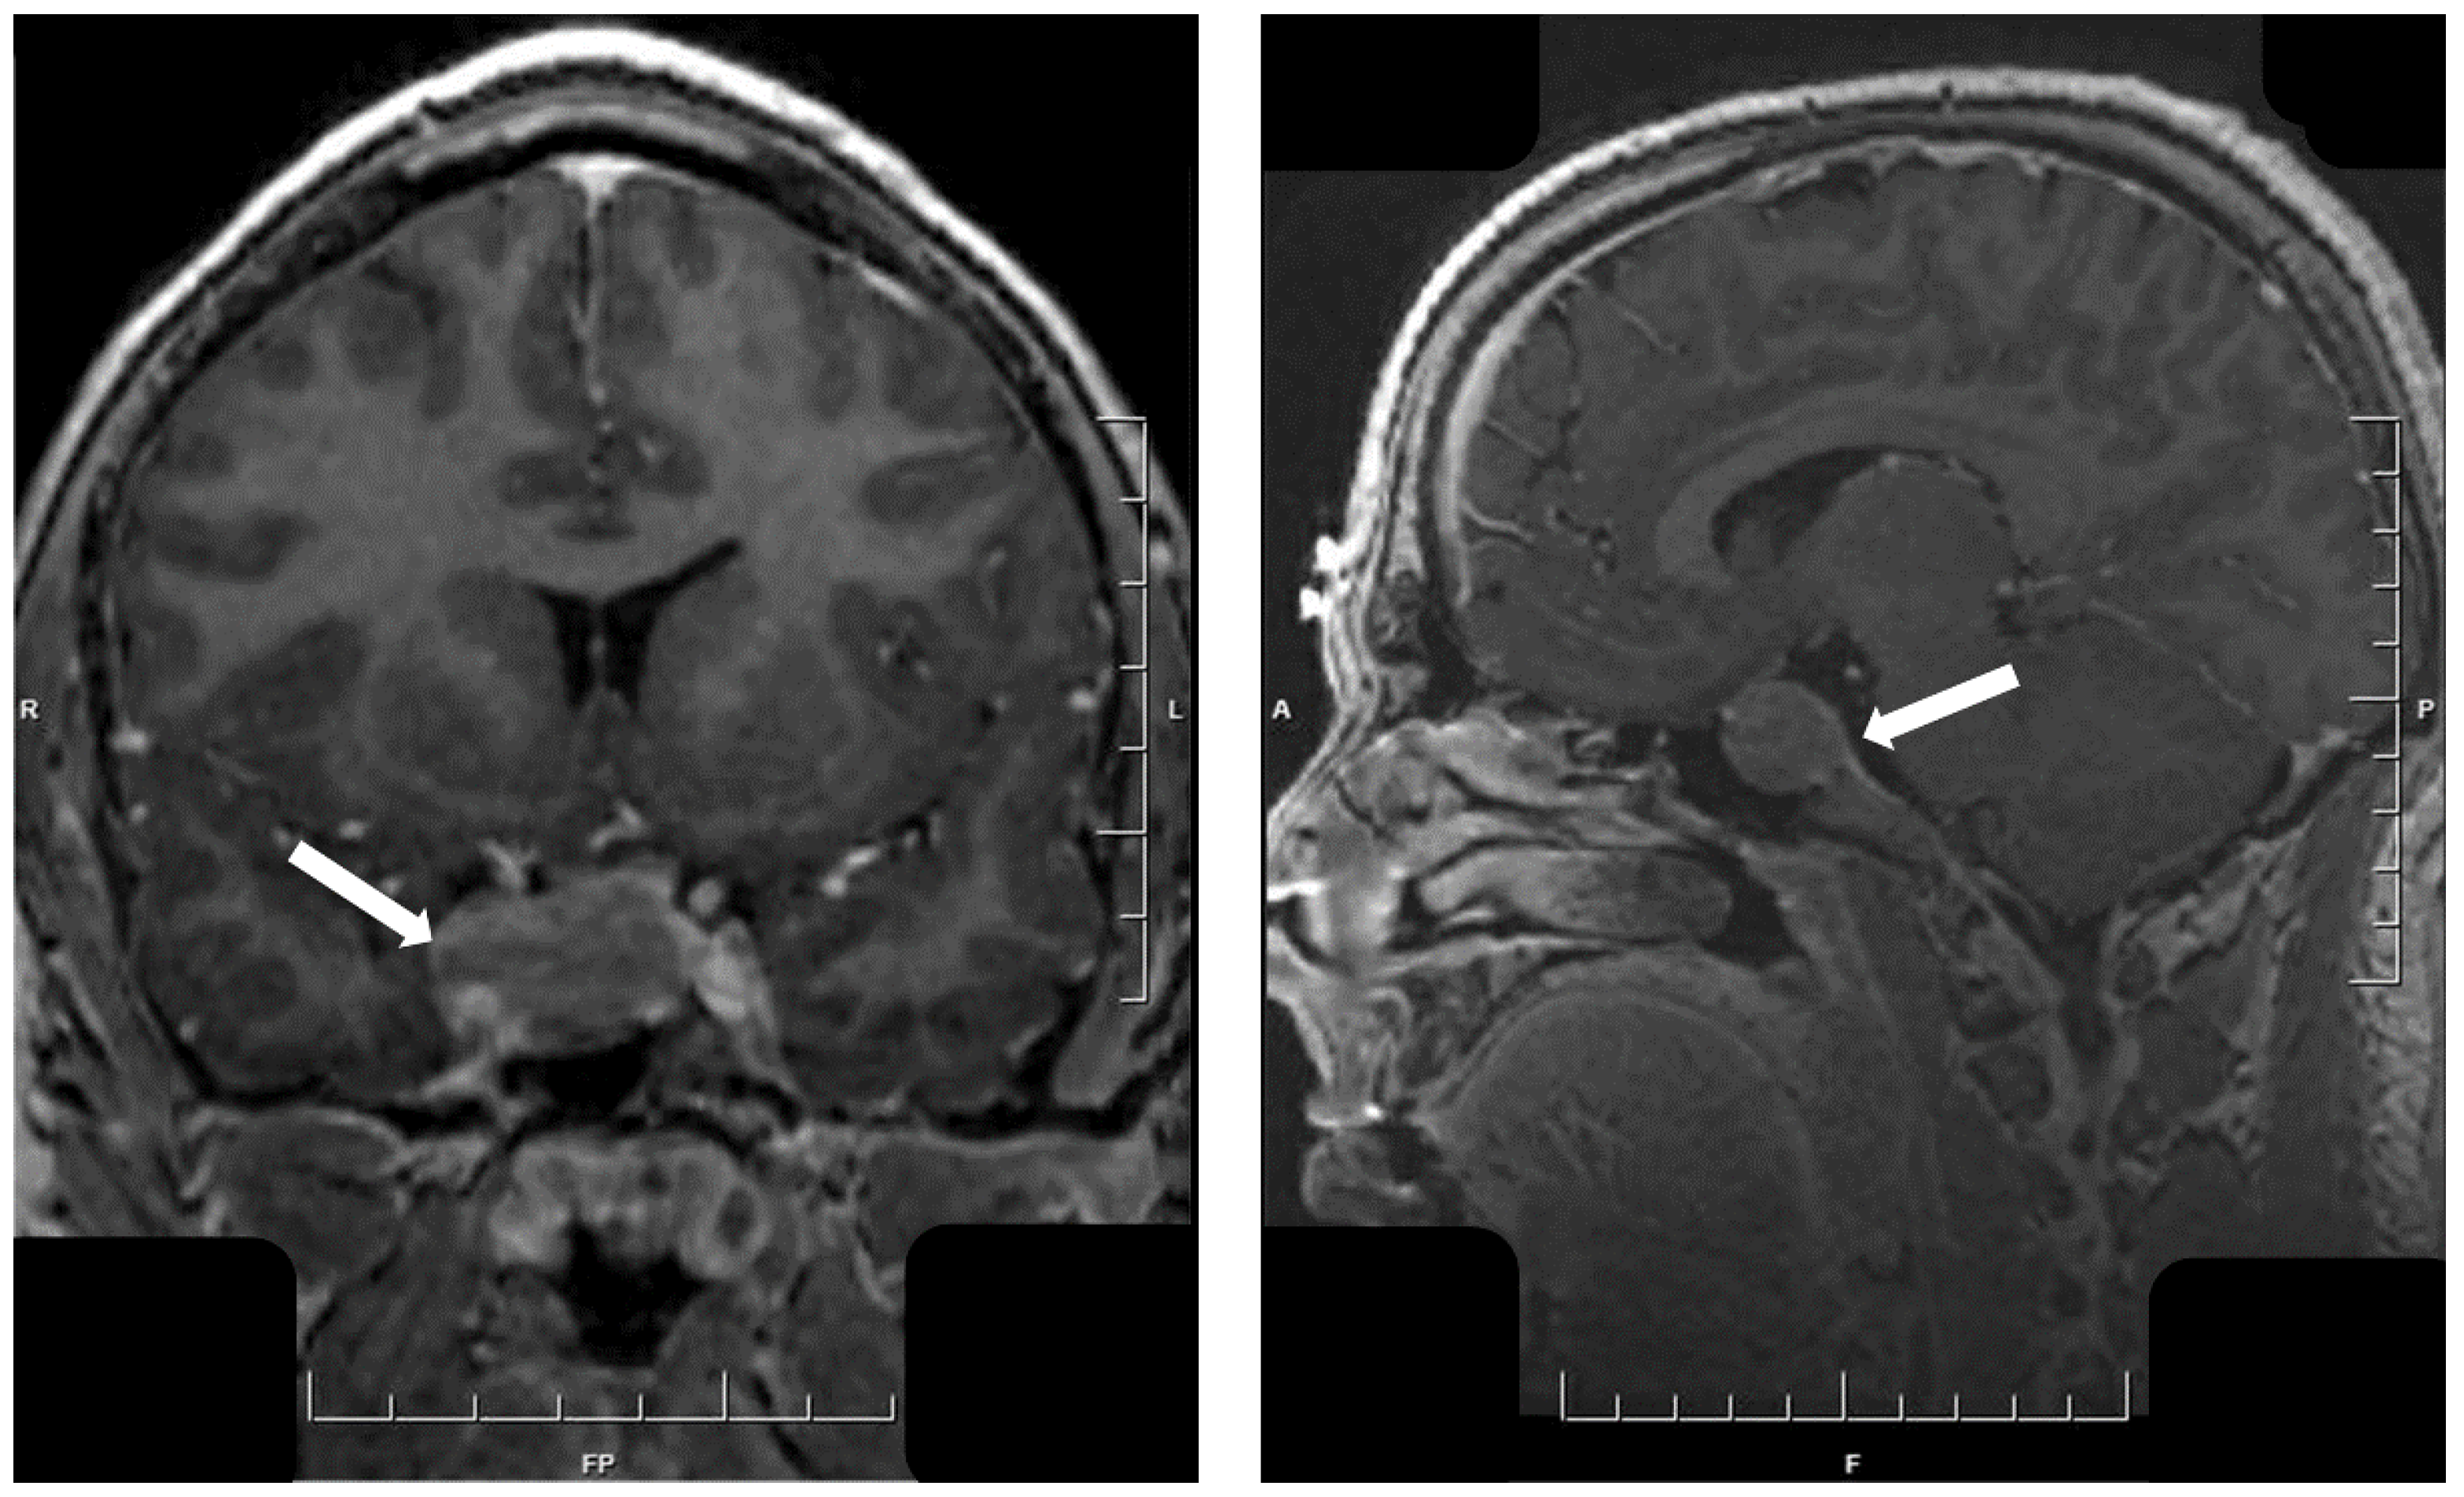

5. Hypothalamic Tumors

- Asa, S.L.; Mete, O. Hypothalamic Endocrine Tumors: An Update. J. Clin. Med. 2019, 8, 1741. [Google Scholar] [CrossRef]

- Asa, S.L.; Scheithauer, B.W.; Bilbao, J.M.; Horvath, E.; Ryan, N.; Kovacs, K.; Randall, R.V.; Laws, E.R.; Singer, W., Jr.; Linfoot, J.A.; et al. A case for hypothalamic acromegaly: A clinicopathological study of six patients with hypothalamic gangliocytomas producing growth hormone-releasing factor. J. Clin. Endocrinol. Metab. 1984, 58, 796–803. [Google Scholar] [CrossRef]

- Felix, I.; Bilbao, J.M.; Asa, S.L.; Tyndel, F.; Kovacs, K.; Becker, L.E. Cerebral and cerebellar gangliocytomas: A morphological study of nine cases. Acta Neuropathol. 1994, 88, 246–251. [Google Scholar] [CrossRef]

- Puchner, M.J.A.; Lüdecke, D.K.; Saeger, W.; Riedel, M.; Asa, S.L. Gangliocytomas of the sellar region—a review. Exper. Clin. Endocrinol. 1995, 103, 129–149. [Google Scholar] [CrossRef] [PubMed]

- Cossu, G.; Daniel, R.T.; Messerer, M. Gangliocytomas of the sellar region: A challenging diagnosis. Clin. Neurol. Neurosurg. 2016, 149, 122–135. [Google Scholar] [CrossRef] [PubMed]

- Akirov, A.; Asa, S.L.; Amer, L.; Shimon, I.; Ezzat, S. The clinicopathological spectrum of acromegaly. J. Clin. Med. 2019, 8, 1962. [Google Scholar] [CrossRef]